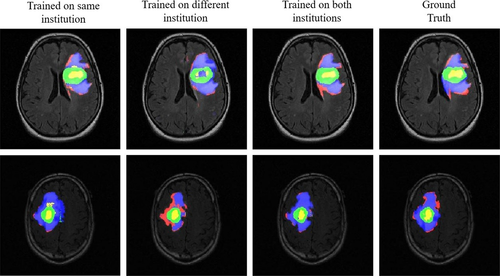

Autoři článku vybrali 44 pacientů s glioblastomem (GBM), kteří měli k dispozici předoperační údaje (MRI) a též údaje o prežití, ze dvou institucí ze souborů údajů The Cancer Imaging Archive. Obrázky byly manuálně anotované naznačením každé nádorové složky, aby se vytvořila základní pravda (ground truth). Aby automaticky rozdělili nádory u každého pacienta, vyškolili tři CNN: (a) jeden s použitím údajů o pacientech z té jisté instituce jako údaje z testů, (b) jeden s použitím údajů o pacientech z jiné instituce a (c) s použitím údajů o pacientech z obou institucí. Dále opomenineme jen výsledky zohledňující přesnost algoritmu, bez zaměření se na odchylky různých institucí.

Dice coefficient se bežně používa pro porovnávání výsledků z algoritmů proti skutečnému hodnocení specialistou. Pro model trénovaný na obou institucích je přiměřený dice coefficient 0.75 ± 0.13 pro Class 2 (na obrázku zelený región). Tyto výsledky můžeme považovat za velmi dobré, a těšit se na potenciální aplikace těchto algoritmů v medicínské praxi.